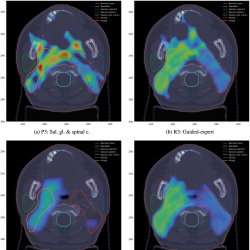

Fig. 7

Plan 3. Dose distributions for $Z=75$ (left) and $Z=91$ (right). Brown: Normal tissue. Pink: Mandible. Green: Salivary gland R. Blue: Salivary gland L. Cyan: Spinal cord +3 mm. Red: PTV54. Orange: PTV60.

7, the dose distributions for this plan on two exemplary cross sections of the 3D model of the patient irradiated part (head and neck).

In Plan 3, the average dose deposited in the right and the left salivary gland is 13.94 Gy and 13.14 Gy, respectively. This is much lower than the maximal admissible value of 26 Gy, while the maximal dose deposited in the spinal cord +3 mm is 24.06 Gy (the maximal acceptable value is 50 Gy). Although Plan 1 and Plan 2 offer slightly lower doses in respective priority protected OARs (the salivary glands in the first case, and the spinal cord +3 mm in the second case), Plan 3 well balances the doses delivered to both salivary glands and to the spinal cord +3 mm.